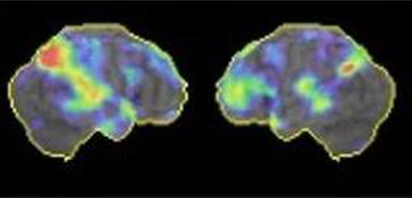

* アミロイドPET(図2):当院で実施可能です。アルツハイマー病の原因物質と考えられているアミロイドβプラークが、脳内に溜まっているかどうかを調べる検査です。抗アミロイドβ抗体薬を使用するには、アミロイドPETが陽性である必要があります。

図2 アルツハイマー型認知症のアミロイドPET